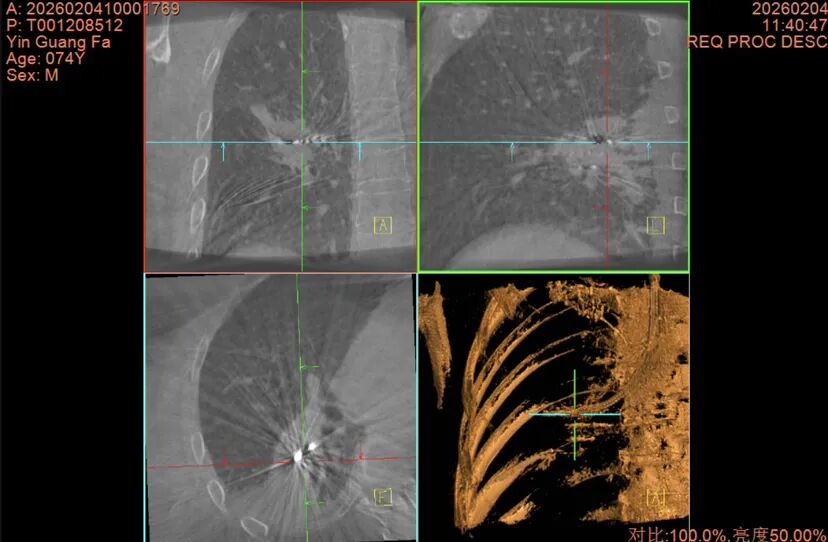

术中C臂CT影像

术中,团队在患者全麻插管状态下先行EBUS-TBNA,并通过现场细胞学评估排除淋巴结转移可能,同时取出组织送病理确诊,确认患者具有接受射频消融手术的指征。随后,团队使用细支气管镜经支气管建立肺实质抵达结节隧道,并经C臂CT及径向超声确认到达结节后,取材进行活检,经过现场细胞学评估结节为恶性细胞。组送病理再次确诊后,团队决定立即行射频消融,消融过程中利用C臂CT实时观察消融范围及探针位置。

手术过程顺利,患者术后无并发症。术后48小时复查CT时,发现消融范围全覆盖病灶并及周围1cm正常组织处,消融效果满意。此次麻醉手术科与胸外一科气管镜室团队协作,实现了安全微创诊疗。目前,该患者已出院。